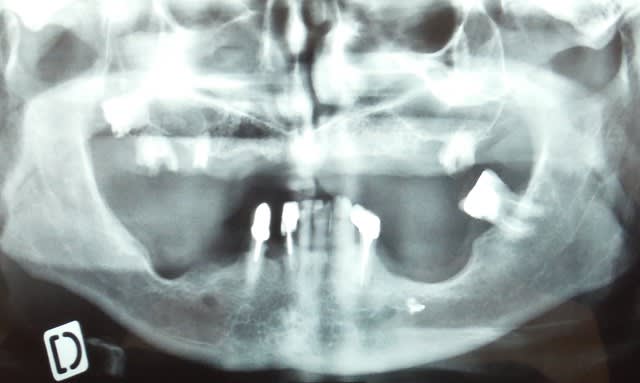

Pour les cas résorbés on verra peut être en septembre octobre. Faut que le devis passe et faire un peu de ménage.

Dscf0630 i2do56 - Eugenol